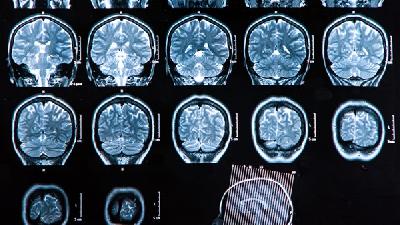

我们都知道脑瘫疾病是很难治疗的疾病,但是患者家属也不要放弃治疗,脑瘫疾病在治疗上需要多种治疗方法配合治疗才能有好的效果,下面请专家进讲中老年人脑瘫手术治疗怎么样?通过专家的讲解看看能否帮助到患者及家属。

神经外科治疗主要针对脑瘫所产生的肌肉痉挛(肌张力增高)、手足徐动、扭转痉挛、振颤、失调等症状,分为针对大脑、小脑、脊髓的中枢手术方式和针对脊神经和四肢周围神经的周围手术方式。

中枢手术方式中的立体定向脑细胞核损毁术、脑刺激术、脑移植术等由于效果不稳定且价格昂贵,在临床上基本不采用,不是治疗脑瘫的常规手术方法。

周围手术方式中选择性脊神经后根切断术(SPR手术)和周围神经缩窄术是目前治疗脑瘫的主要手术方法。SPR手术的历史较长,对解除四肢的肌肉痉挛状态疗效肯定。但此手术的创伤较大,要切除一部分脊椎骨,有可能对患者以后的生长发育产生不良的影响(脊柱前凸等),同时手术后的严重并发症时有发生,如四肢变得松软无力,运动功能不如术前等,不易被康复科医生和家属所接受。

所以,手术前要详细分析患者的病情,手术中尽量少切除脊椎骨,采用术中神经和肌肉的功能监测和分析,严格掌握手术适应症,手术才能取得良好的治疗效果,减少并发症的发生。